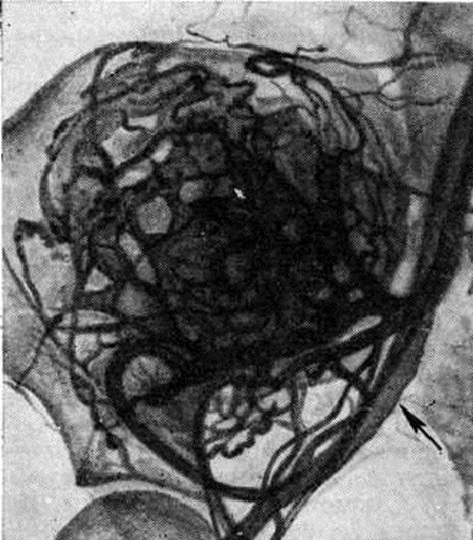

При Гемангиома кости никогда не наблюдается сплошного остеолиза или крапчатых склеротических включений, характерных для метастазов опухолей в позвоночник. При компрессионном переломе позвонка с целью дифференциальной диагностики метастаза опухоли и Гемангиома проводят ангиографию. Так, например, в результате ангиографии в теле поясничного позвонка (L3) вместо предполагавшегося метастаза опухоли была обнаружена кавернозная Гемангиома (рисунок 2).

Рис. 2. | ||

Дифференциально-диагностические трудности, возникающие при глубоком расположении Гемангиома в мягких тканях, могут быть разрешены при помощи ангиографии (рисунок 4).